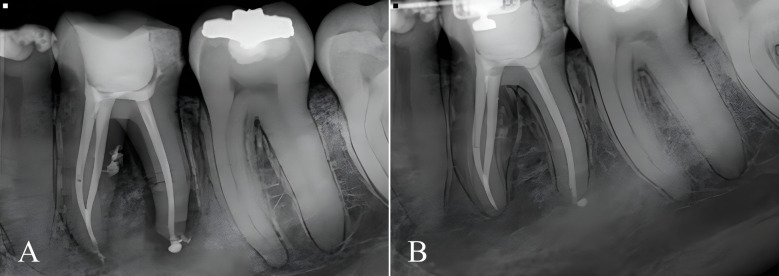

Materials and method: Fifty mandibular molars were selected and instrumented with ProDesign Logic files. First, mechanized patency was performed with a 25/0.01 instrument; if it was easily achieved, a larger diameter instrument was chosen (30/0.01, 35/0.01, or 40/0.01) that best matched the apical foramen. Then, a respective shaping file corresponding to the patency file was selected for instrumentation. Irrigation was carried out with saline solution and 2% chlorhexidine gel. A 17% EDTA solution was used for the final irrigation and agitated with the EasyClean system. A device was used to standardize the initial, final, and subsequent digital radiographic examinations for the follow-up. A 3-level scoring system was used for evaluation, in which score 1 indicated complete lesion healing, score 2 incomplete healing, and score 3 no healing.

Results: There was no significant difference between the frequencies of scores 1 and 2 assigned at the two assessment time points (p > 0.05). Complete healing (score 1) was observed in 58%, incomplete healing (score 2) in 42%, and no healing (score 3) in 0% of cases.